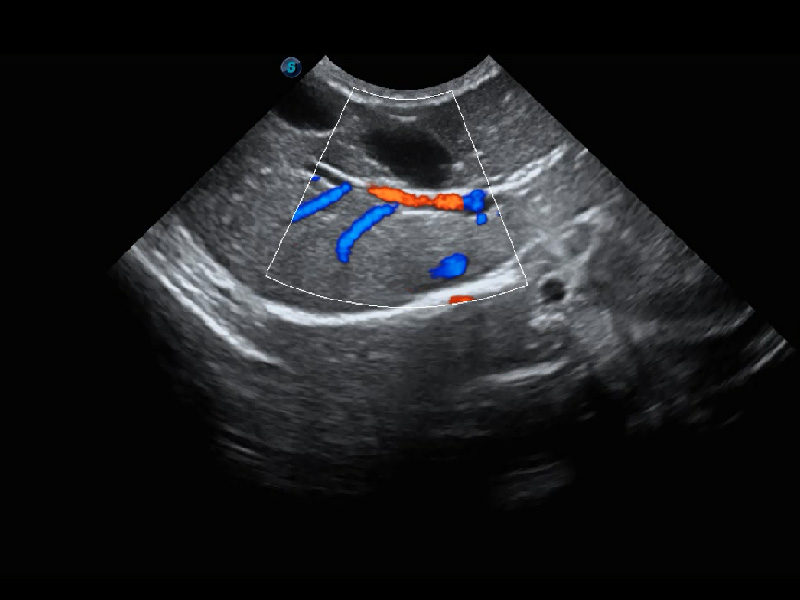

(猫)髂动脉血流频谱

4T血流成像 微察秋毫

融合不同血流成像技术的优势,即可以提升血流成束性,同时可提高血流的视觉敏感性。

PDI 能量多普勒血流

提供高灵敏度和空间分辦率的血流图像,获得更加真实和丰富的诊断信息。

SR Flow 高分辨率血流成像

能够清晰显示细小、低速血流图像,获取传统彩色多普勒技术难以得到的细节和信息。